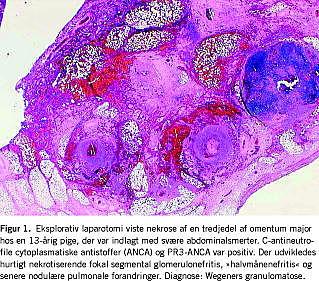

Wegeners granulomatose (WG) ses sjældent hos børn og karakteriseres ved nekrotiserende granulomatøs inflammation af små og mellemstore kar (Figur 1). Femårsincidensen er beregnet til 0,1 ud af 100.000 med en gennemsnitsalder på 14-15 år [7]. Den klassiske symptomtriade er destruktive inflammatoriske læsioner i øvre og nedre luftveje samt GN. Symptomerne er ofte ledsaget af vægttab, træthed og feber. Tilstedeværelsen af høj titer af proteinase 3 (PR3)-antineutrofile cytoplasmatiske antistoffer (ANCA) og positiv cytoplasmatisk ANCA (c-ANCA) støtter diagnosen. I tidligere publikationer har man peget på en relativt øget risiko for subglottis stenose og nasale deformiteter ved juvenil debut samt lavere risiko for renal (9%) og pulmonal (22%) involvering initialt. I et nyligt publiceret studie med 25 juvenile WG-patienter har dette dog ikke kunnet bekræftes, idet 22 havde GN, og en havde subglottisstenose ved sygdommens opståen [7].